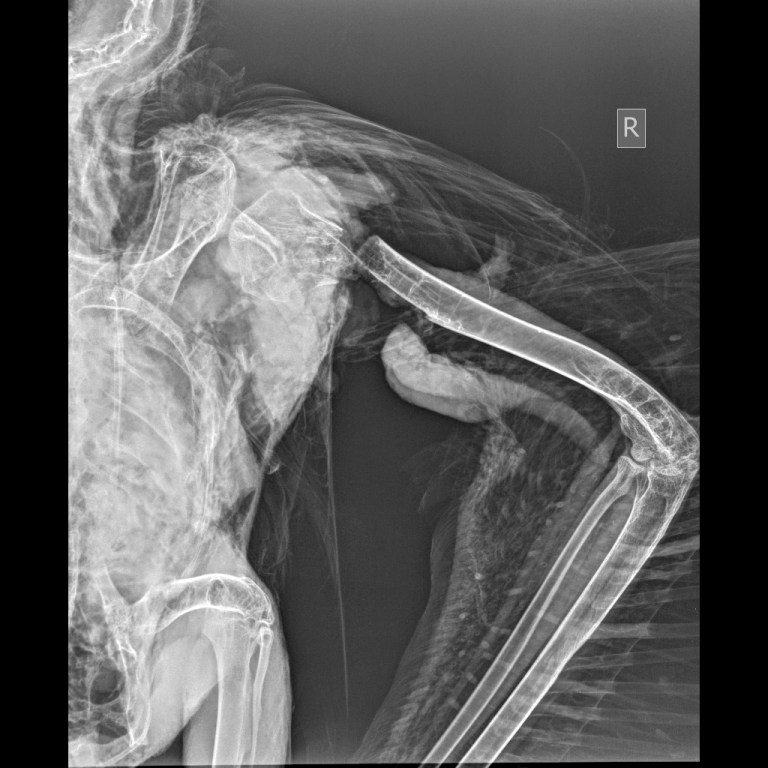

Ακτινογραφία του νεκρού μαυρόγυπα με ακρωτηριασμένη τη δεξιά φτερούγα

Το περιστατικό διαπιστώθηκε τόσο χάρη στις κάμερες του εγκατεστημένου συστήματος αποτροπής πρόσκρουσης που είναι εγκατεστημένο στην ανεμογεννήτρια, όσο και χάρη στον πομπό που έφερε το πουλί. Κατά την πρόσκρουση με το πτερύγιο της ανεμογεννήτριας το πουλί ακρωτηριάστηκε και η δεξιά του φτερούγα αποκόπηκε από το σώμα. Το ακρωτηριασμένο πουλί παρέλαβαν την επόμενη μέρα υπάλληλοι της εταιρίας στην οποία ανήκει το αιολικό πάρκο και το παρέδωσαν στη Δασική Υπηρεσία, η οποία με τη σειρά της ενημέρωσε τον ΟΦΥΠΕΚΑ, έτσι ώστε να γίνουν οι απαραίτητες ενέργειες για την εξακρίβωση των συνθηκών υπό τις οποίες συνέβη το περιστατικό.